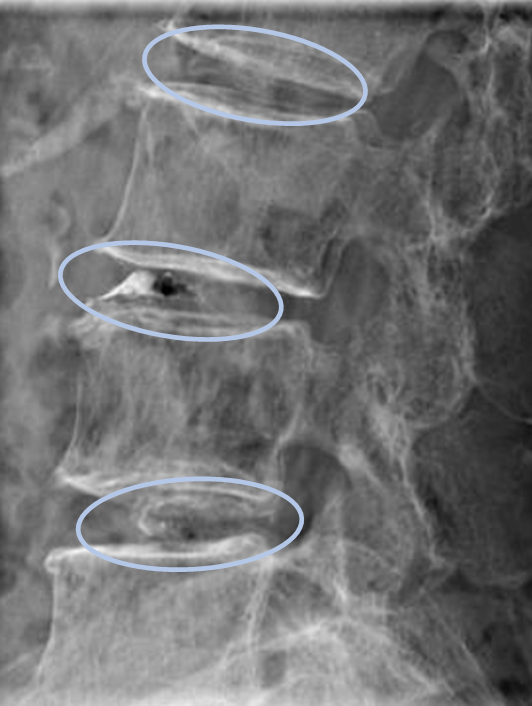

患者様と相談の元、L3/4,4/5,5/sにセルゲル法を施行

DiscoGelを入れた後の画像になります。